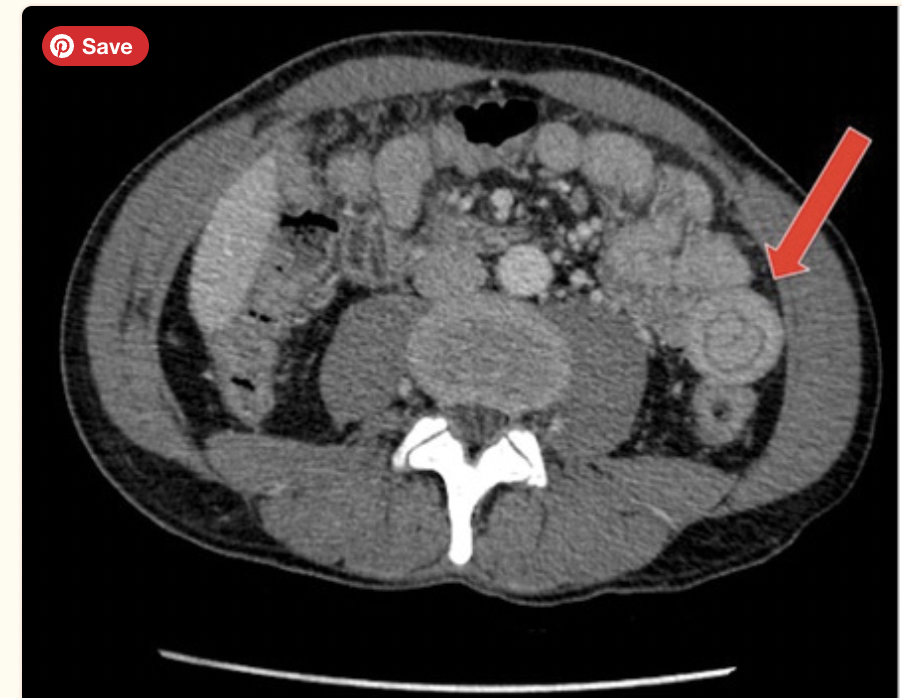

intussusception

target sign

target sign or bulls eye